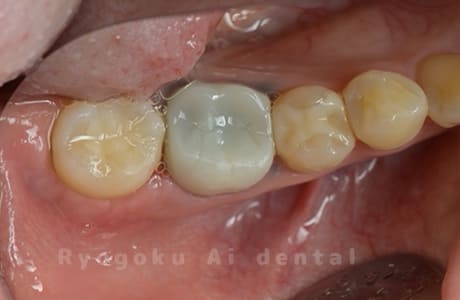

Case27

-

重度カリエス

歯牙移植咬合面術前 -

移植する親知らず

歯牙移植術直後咬合面

歯牙移植術後咬合面

歯牙移植術前側面

歯牙移植術中側面

歯牙移植術後側面

- 原因

- 重度カリエス

- 治療内容

- 自家歯牙移植、部分矯正

- 治療費用

- 220,000円(移植費用)

110,000円(部分矯正費用)

虫歯が大きく、保存不可能となった歯を上の親知らずと交換する自家歯牙移植を行いました。移植歯が小ぶりであったため、部分矯正を行い問題なく噛み合い、経過良好です。